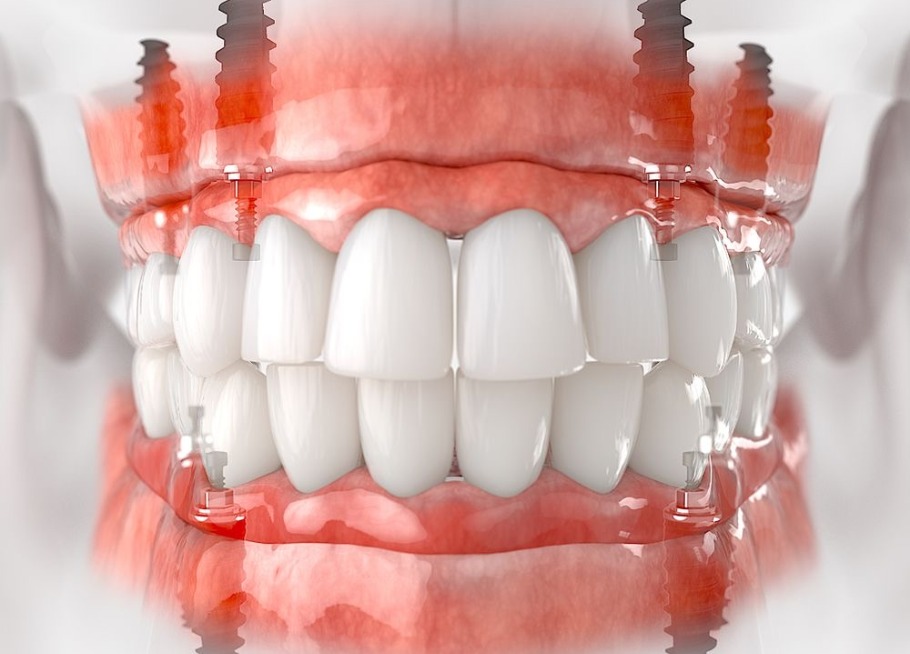

- All-on-4: four implants support a full arch fixed bridge; often immediate loading (temporary teeth same day). Popular for patients with moderate bone loss.

- All-on-6: six implants per arch for extra stability; recommended when bone volume is lower or heavier biting forces are expected.

- All-on-8 / full-arch with 8+ implants: uses more implants for maximum long-term strength and is closer to “traditional” full-mouth rehabilitation.

- Zygomatic implants are anchored into the cheek (zygoma) bone; used when the upper jaw bone is severely resorbed and grafting is impractical. Turkish clinics are experienced in zygomatic protocols.

- Traditional full-mouth (16–20 implants): replacing each tooth individually; more invasive but often the most natural-feeling long-term solution.